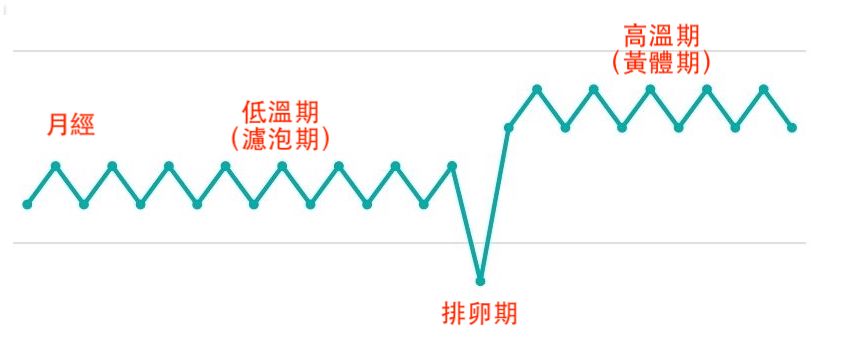

首先,古裕一郎認為,撇除男方因素,女生要容易懷孕,首先要有好體質,跟年紀反而沒有太絕對的關係,尤其是靠中醫好好調養,也極有可能在大齡年紀幸運懷孕。那怎麼樣是好懷孕的體質呢?古裕一郎在著作《大齡女子也能打造好孕體質》中解釋:「月經週期介於28~30天之間,低溫期和高溫期分明,是基礎體溫的理想型態。」

低溫期(濾泡期):14天左右,體溫大約是36.2℃~36.4℃。

排卵期:1~2天,低溫期接近尾聲時,體溫會稍微下降,接著很快上升0.3℃~0.5℃。

高溫期(黃體期):12~14天。體溫36.7℃以上(理想是36.7℃~37℃)。

月經期:5~7天,月經開始第一天就會一口氣下降0.3℃~0.5℃。